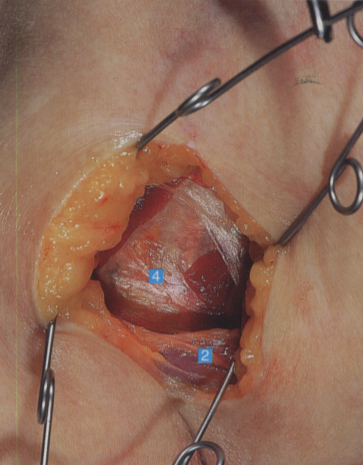

三角肌和胸大肌上的皮下组织,如果仔细观察皮下脂肪边缘,会隐约见到头静脉1. 头静脉;2. 胸大肌

1. 头静肌;2. 胸大肌;3. 三角肌;

4. 肱二头肌筋膜;5. 肱二头肌短头;